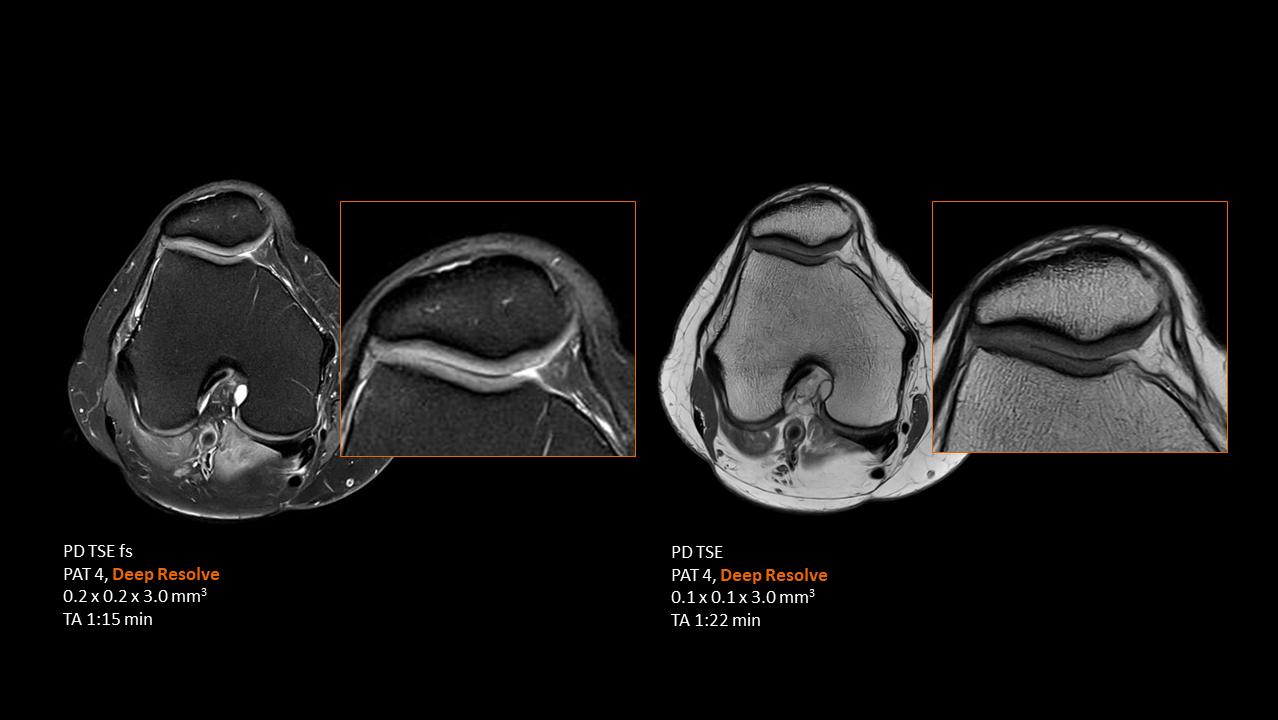

Deep Resolve will be at the forefront of the revolution in MRI acceleration. Deep Resolve will enable our fastest MRI, with images that will have extraordinary clarity, higher clinical productivity, and an even better patient experience. This transformational effect of Deep Resolve is now planned to expand to 3D5, unlocking a new dimension in MRI image resolution and speed.